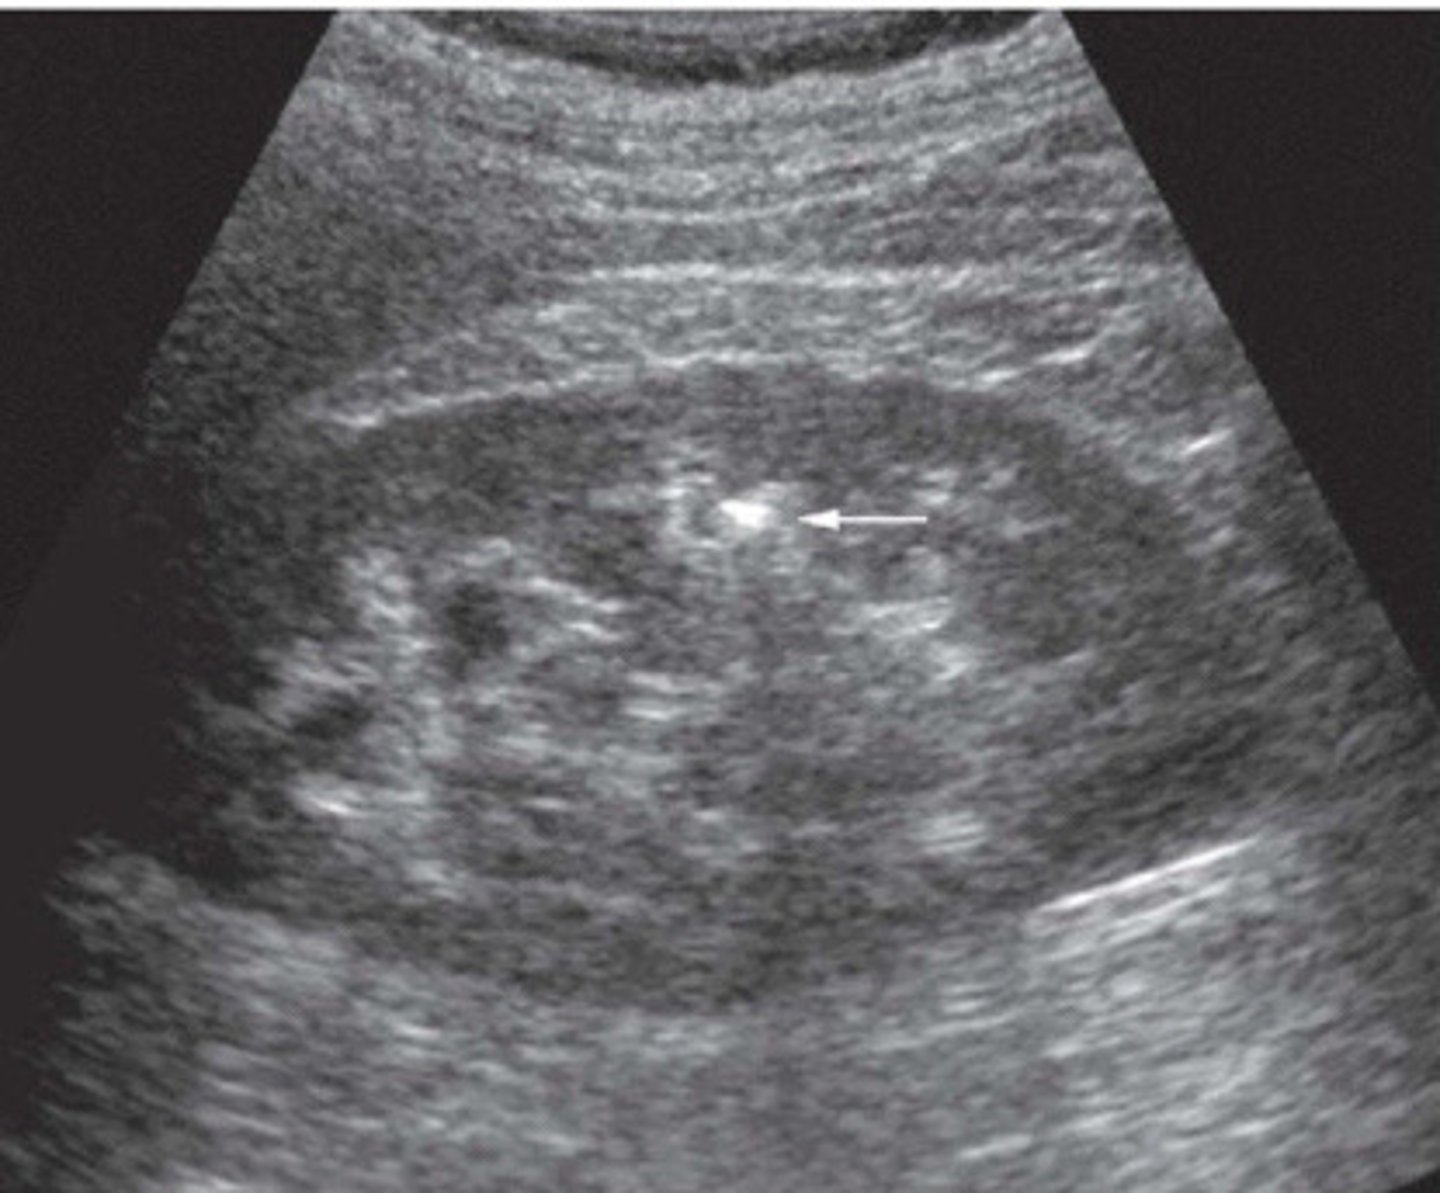

Stone now identified with the twinkle artifact

What does this image show

<p>What does this image show</p>

When a stone is located in the sinus region, it is hard to determine if it is a stone bc it will blend into the hyperechoic sinus. You can use colour or power Doppler to look for a twinkly artifact a stone will give off

Explain how you can use the twinkling artifact to your advantage when suspicious of a stone in the sinus region

Colour reverberation

What is the twinkling artifact

Colour or power Doppler

What mode do you have to use in order to be able to see the twinkling artifact